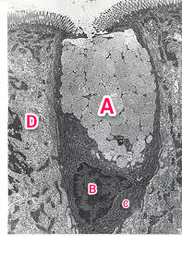

Parietal cell TEM "NOTICE apical occluding junction"

A : Lumen B : Microvilli C : Intracellular canaliculas D : Mitochondria